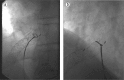

Transjugular intrahepatic portosystemic shunt (TIPS) extension far into the inferior vena cava (IVC) or the right atrium may complicate or preclude orthotopic liver transplantation depending on the space available for placement of a hemostatic clamp in the suprahepatic IVC. Until 2004, most TIPS were performed with bare metal stents, which integrate into the vessel wall, making percutaneous or intraoperative repositioning uncertain. Most TIPS are currently created with stent grafts that have an outer fabric to increase shunt patency and prevent endothelial ingrowth. We describe the first known manipulation of a covered stent graft prior to transplantation. The stent graft, which extended well into the IVC, was snared from a femoral approach and deflected caudally in order to document feasibility and nonadherence to the vein wall prior to definitive surgical planning of liver transplantation. Provisions were made for endovascular retraction during actual transplant surgery 9 weeks later, but this became unnecessary when manual retraction of the exposed liver enabled suprahepatic IVC clamping. Due to the nonadherent nature of the outer graft material, compared with a bare metal stent, extension of a stent graft into the IVC or right atrium may not preclude transplantation, and intraoperative endovascular retraction may be considered.